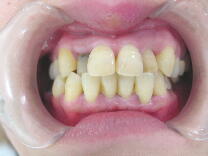

A、セラミック冠で治療した症例(上顎前歯部4本のみ治療)

切歯2本は神経のない無髄歯の為、徐々に変色をきたしていました。左右の側切歯は保険

のプラスチック前装冠です。表面がプラスチックの為時間の経過と共に材料が徐々に劣化 して変色をきたしています(下左図)。ひどい場合には削れて裏打ちの金属が見えてくる こともあります。 ![]() ![]()

歯肉状態の改善をはかり、十分なるブラッシングができるようになった後、それらをセラ

ミック冠で修復しました。